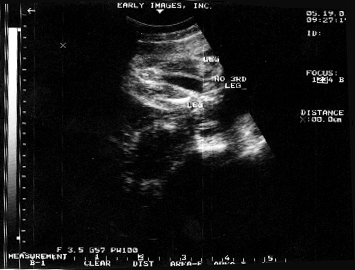

LOOK AT ME IN THE BELLY